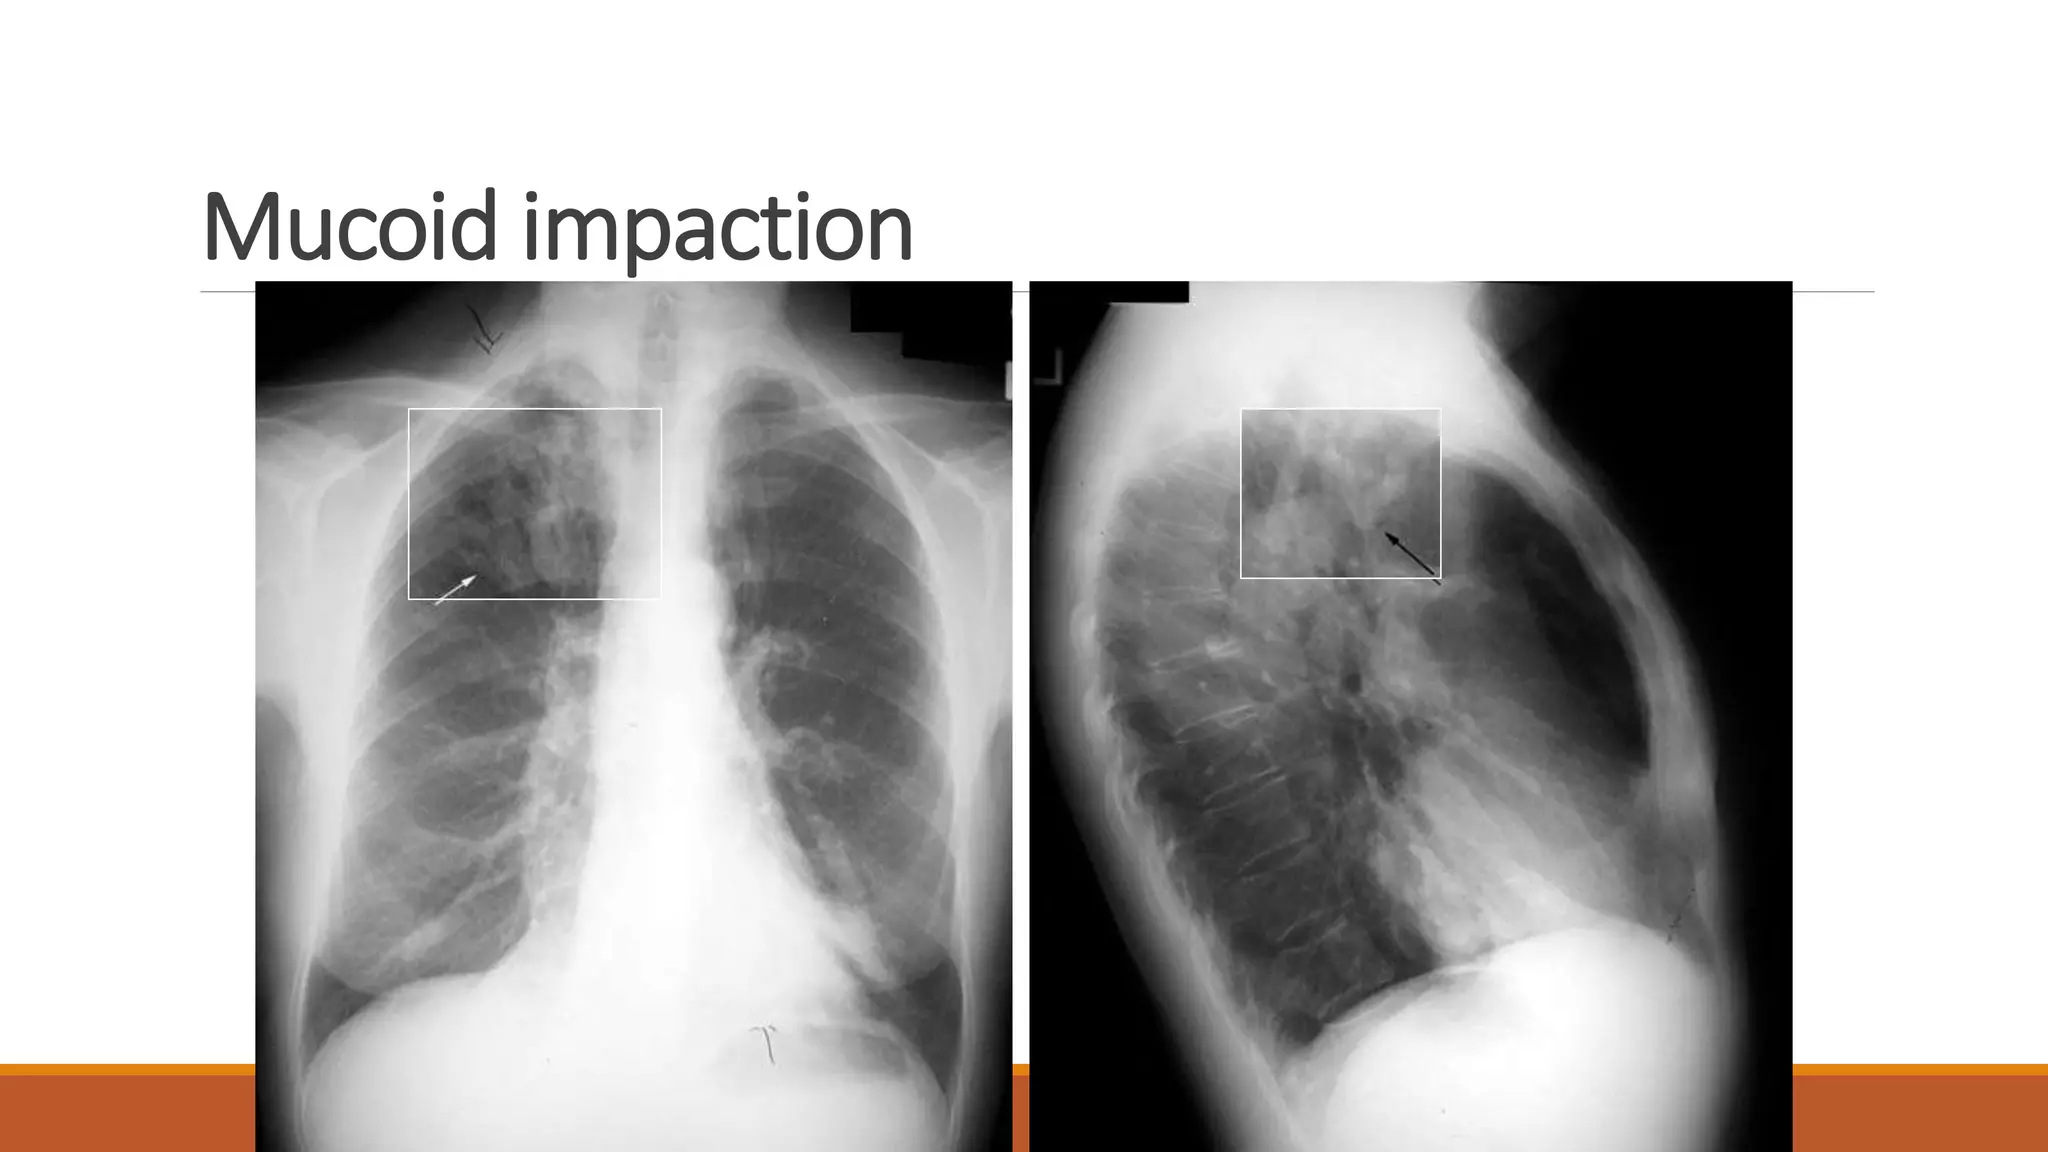

Mucoid impaction

Fluid filled bronchi

Bronchial wall thickening

Multiple air fluid levels